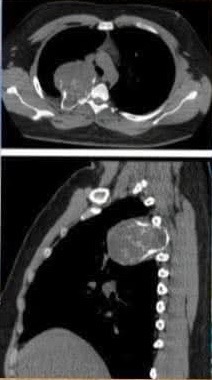

Hello, my name is Dora, and I am fundraising for my cousin who means so much to me and my family. This October, he will be turning 21 years old. Instead of celebrating this milestone with joy, he is facing one of the hardest battles of his life. He was recently diagnosed with chondrosarcoma osteo stage 2, a rare form of bone cancer.

Hola, mi nombre es Dora y estoy recaudando fondos para mi primo, quien significa tanto para mí y para mi familia. Este octubre cumplirá 21 años. En lugar de celebrar este gran momento con alegría, está enfrentando una de las batallas más duras de su vida. Recientemente fue diagnosticado con condrosarcoma óseo en etapa 2, un tipo raro de cáncer de hueso.